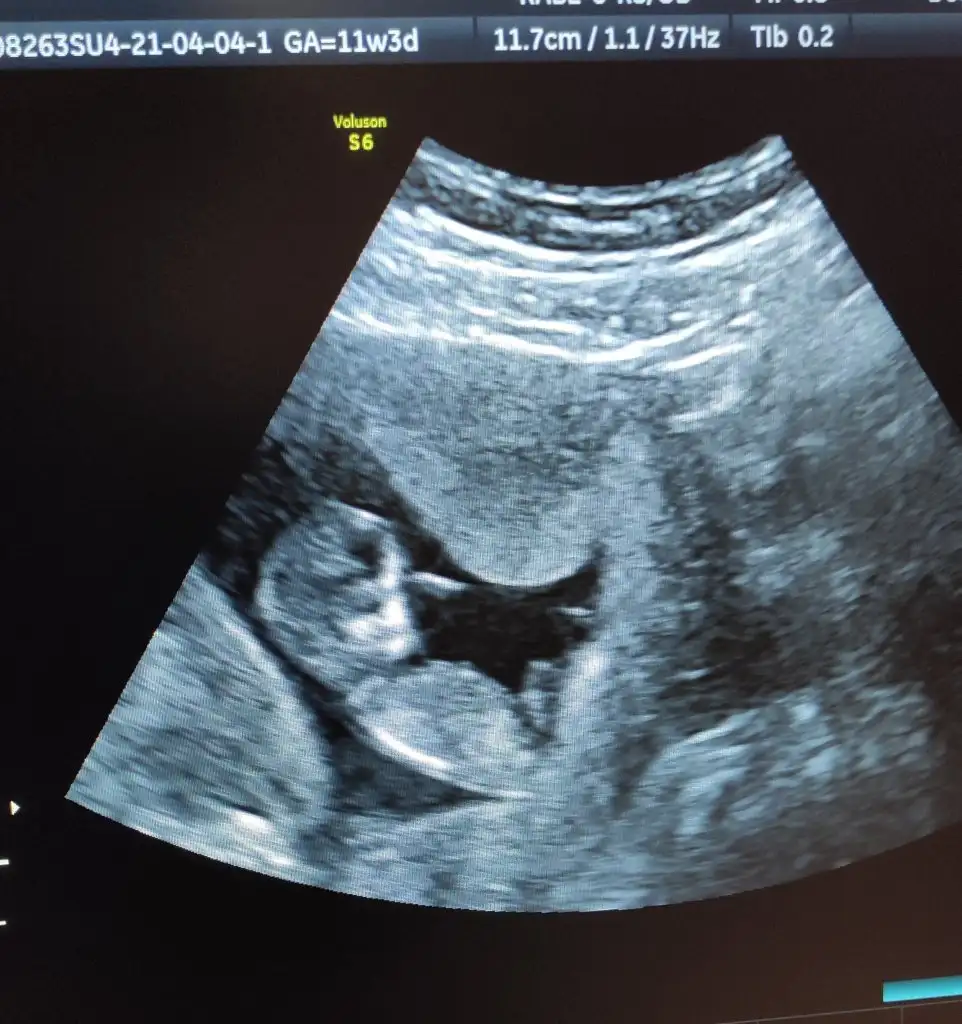

Canım bende gittim bugün ikili teste çok şükür iyi bebiş..Ölçümlerine iyi dedi doktorum.Kani da verdim..Fetal DNA icinde öneririm dedi..Görüşmüştüm zaten genetik merkezi ile bugün eve gelip kanı da aldılar..10-15 güne çıkar dediler...

Cinsiyet için bişey demedi doktoruk erken dedi 😅

Eklentiler

• IMG_20210405_160828.webp

IMG_20210405_160828.webp

55,7 KB · Görüntüleme: 33